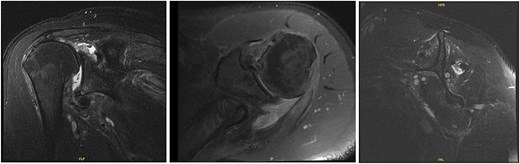

The patient was determined to be a candidate for surgical intervention given his age, ongoing symptoms, and continued dysfunction. Expectations of surgical treatment were discussed, including the possibility of a less reliable outcome regarding his right shoulder given his previous surgical history. Six weeks after injury, the patient underwent left shoulder rotator cuff arthroscopic repair. Findings included full-thickness tears of the subscapularis, supraspinatus, and infraspinatus, with glenohumeral chondromalacia (Fig. 7). He was maintained in a Frank Stubbs immobilizer for 6 weeks and then started physical therapy.

Intraoperative imaging of left shoulder arthroscopic debridement and rotator cuff repair including findings of full-thickness supraspinatus and subscapularis tendon tears, which subsequently were repaired.